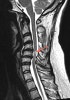

- MRI : 주위 연부조직의 상태뿐만 아니라 척수 압박의 직접적인 원인과 척수 자체의 상태를 나타나는 장점이 있습니다.

MRI : 경추 척수증(Cervical myelopathy)